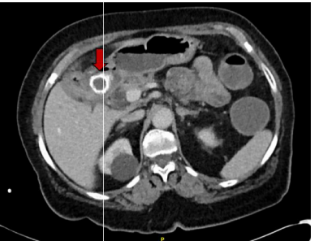

抽血检查发现患者炎性标记物升高,白细胞计数15.6x109,C反应蛋白(CRP)为67mg/L,肝功能中胆红素,碱性磷酸酶,谷丙转氨酶等均升高,提示肝功能异常,有梗阻性黄疸可能。腹部CT检查发现十二指肠近端和结肠远端分别两块结石,大小约3cm和3.3cm(如图1和图2);同时报告了胆囊结石伴急性胆囊炎,胆总管扩张,约1.7cm,验证了胆囊结石引起的Bouveret综合征。

图1 十二指肠近端梗阻,梗阻原因为结石嵌顿